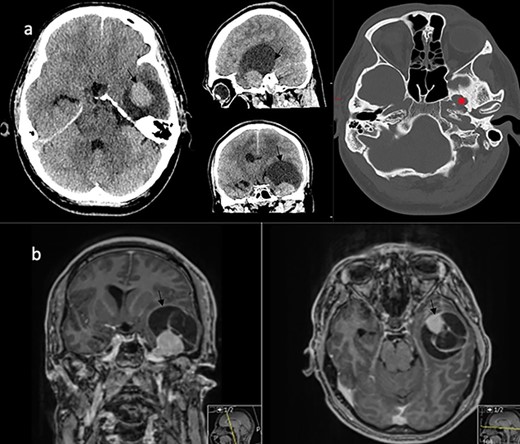

A 32-year-old man presented with a 4-week history of worsening headaches, and a 1-week history of nausea and vomiting associated with memory problems over a period of months. Neurological examination was unremarkable. Computed tomography (CT) scan with contrast revealed a left temporal enhancing lesion with enlargement of the foramen ovale (Fig. 1a) and an magnetic resonance imaging (MRI) scan confirmed the presence of a large lesion (43 x 45 x 54 mm) lying in the temporal fossa, with mixed cystic and solid enhancing components (Fig. 1b). After discussion at the neuro-oncology multi-disciplinary meeting, a decision was made for surgical resection of the lesion.

Imaging characteristics of the V3 lesion. (a) CT scan axial, sagittal and coronal views (brain and bone window) showing the lesion in the left middle fossa with enlargement of the foramen ovale (asterix). The lesion (arrow) is uniformly enhancing with a large capping cyst causing mass effect. (b) MRI scan coronal and axial views showing a mixed solid and cystic lesion (arrow) in proximity to the Meckel’s cave.